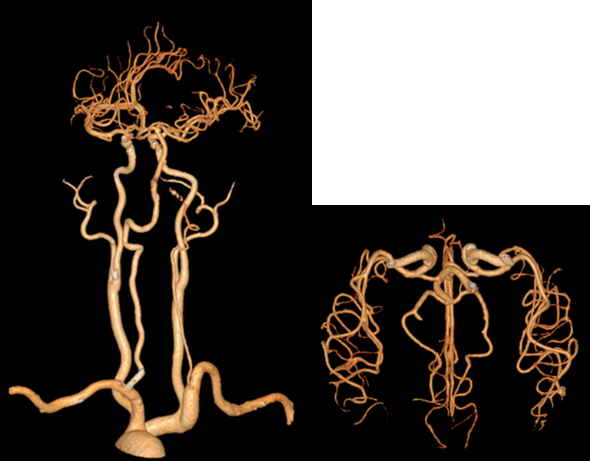

六十多岁的朱先生因“头晕19小时意识不清2小时”来到我院急诊,急诊神经科医师接诊后考虑脑血管疾病,立即行头颈部CTA+CTP检查,判断闭塞血管及梗死面积。影像科张卫国主任团体第一时间完成头颈CTA+CTP后处理,结果提示患者左侧椎动脉V1段起始处次全闭塞,右侧椎动脉V4段闭塞;基底动脉闭塞;双侧椎动脉供血区(双侧小脑、脑干、部分颞叶)缺血性灌注异常。

由于患者错过了4.5小时脑卒中静脉溶栓救治时间,无法溶栓治疗。郝永岗副主任带领神经血管介入团队评估病情后决定在全麻下为患者实施动脉取栓术,挽救处在缺血状态尚未坏死的脑组织。麻醉科李健主任第一时间到达导管室,保障手术顺利进行,术中可见患者基底动脉末端闭塞(基底动脉尖综合征)。医生运用SWIM技术取出黑红色血栓,复查造影显示:基底动脉远端血流通畅,双侧大脑后动脉、小脑上动脉显影。术中发现患者左侧椎动脉起始部重度狭窄,于病变处植入支架一枚,血管狭窄解除,术后送重症医学科继续治疗。